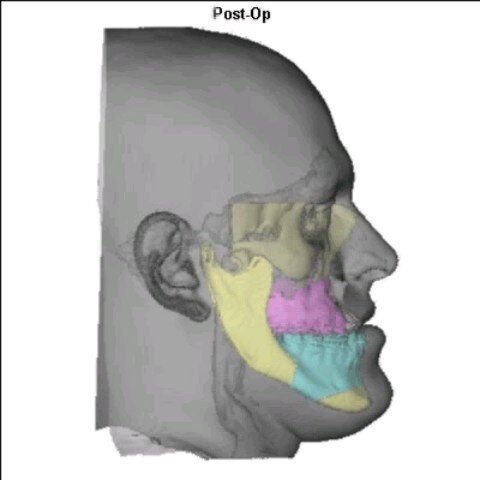

Cirurgia Ortognática

Você sente dificuldade para morder, falar ou até mesmo respirar corretamente? A Cirurgia Ortognática pode ser a solução! Esse procedimento corrige alterações ósseas no maxilar e mandíbula, melhorando a função mastigatória, a harmonia facial e a qualidade de vida.

Dr. Guilherme Rosetti é Cirurgião Bucomaxilofacial e Especialista em Harmonização Orofacial, com sólida formação nacional e internacional. É graduado em Odontologia pela Universidade Federal do Paraná (UFPR) e especialista em Cirurgia e Traumatologia Buco-Maxilo-Facial pela PUC-RS. Possui pós-graduações em Cirurgia Oral Menor (ABO-PR), Artroscopia da ATM (IECS) e Cirurgia Ortognática Minimamente Invasiva (ITC), além de fellowship em Cirurgia da ATM pela JRG Odontologia. É também especialista em Harmonização Orofacial com registro oficial pelo CFO, com formação em Toxina Botulínica e Preenchimento Orofacial pelo Instituto Ziroldo. Conta com diversas habilitações técnicas, incluindo Ozonioterapia, Laserterapia, Sedação Consciente e Venopunção com I-PRF. Completou treinamentos de alto nível como o Virtual Planning in Orthognathic Surgery pela KLS Martin (Alemanha), o L1 MI Orthognathics – ITC Brasil e o curso da SORG Academy em Viena (Áustria), voltado à Cirurgia da ATM. É membro do Colégio Brasileiro de CTBMF e da Latin American Society of TMJ Surgeons (LASTMJS). Com mais de 20 anos de experiência, atua nos principais hospitais de Curitiba, sendo referência nacional em cirurgia ortognática, cirurgia da ATM, implantes, reconstruções ósseas e harmonização facial avançada, com foco em precisão técnica, estética e recuperação funcional de excelência.

Etapa III: cirurgia